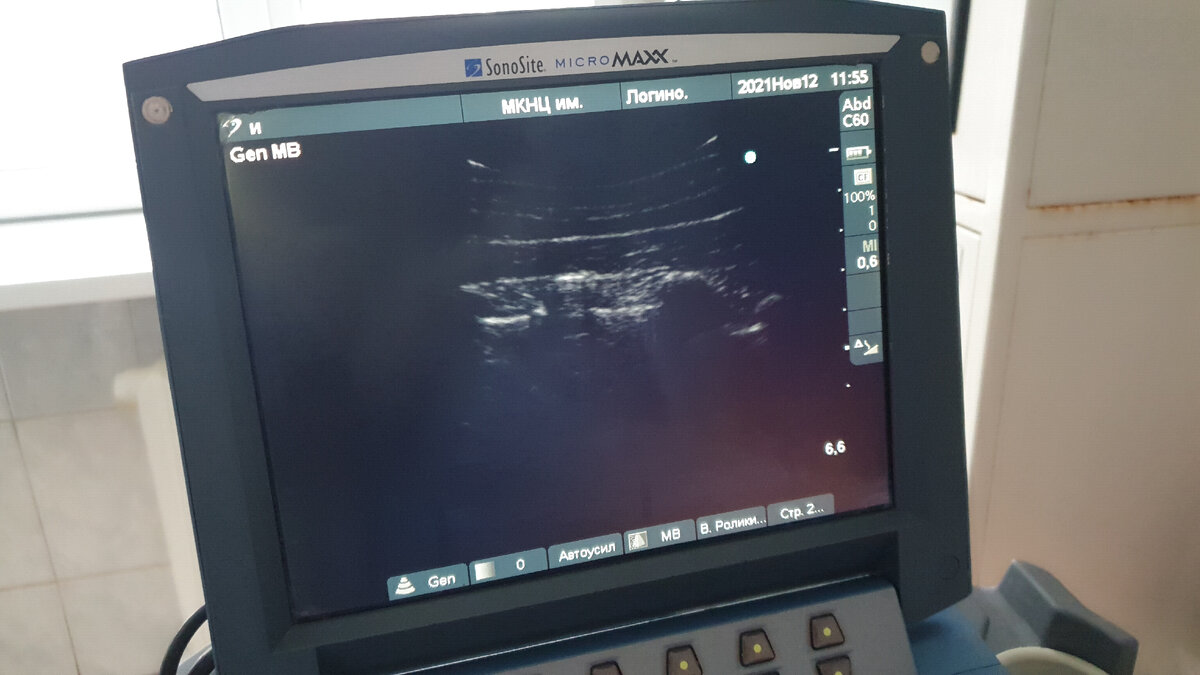

Блокада - введение лекарственного препарата в конкретную точку, которая доставляет наибольший дискомфорт. Внешне процедура похожа на обычный укол. Только применяются немного другие иглы, они как правило больше,  и выполняются под контролем ультразвука или рентгена. Контроль введения обязателен, он обеспечивает безопасность пациенту и позволяет врачу точнее выбрать зону для введения препарата.